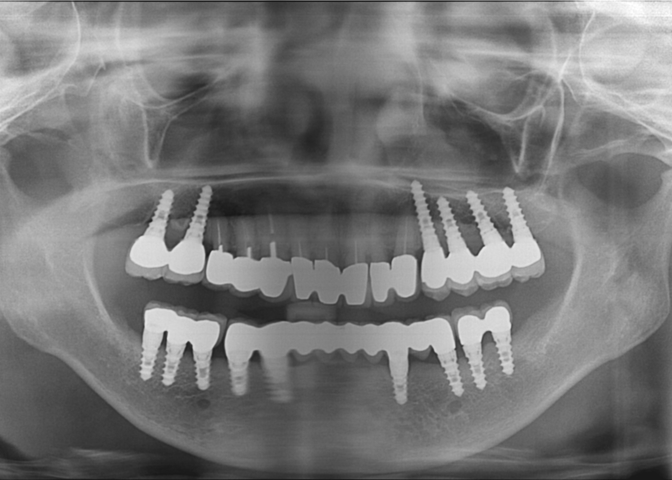

手术日期 | 2008.05.19 |

手术日期 | 2007.07.05 |